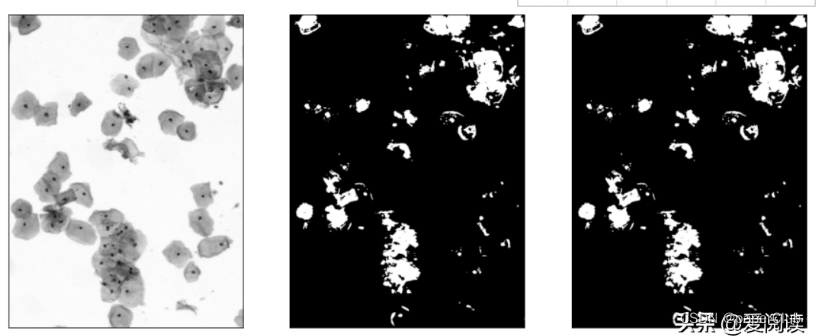

如图,动物细胞主要由细胞质(浅蓝色或浅红色)和细胞核(深蓝色)构成。我们看到的生物细胞颜色会有所不同,有浅蓝色的和浅红色的,颜色不同是由于细胞质和染色液结合后发生了不同的显色反应(主要是由于细胞内环境及PH差异引起),这也反应了细胞所处的阶段或生理转态不同,中间的深蓝色小点就是细胞核。

细胞区域分割:

我们先拿到hsv图像, 完成细胞区域分离:

plt.subplot(131), plt.imshow(img_gray, 'gray'), plt.xticks([]), plt.yticks([])

plt.subplot(132), plt.imshow(img_hsv, 'gray'), plt.xticks([]), plt.yticks([])

plt.subplot(133), plt.imshow(bw_cell, 'gray'), plt.xticks([]), plt.yticks([])

plt.show()

### 获取细胞区域

my_threshold = img_mask_mean - bg_gray_r

_, bw_cell1 = cv2.threshold(img_gray, my_threshold, 1, cv2.THRESH_BINARY_INV)

element = cv2.getStructuringElement(cv2.MORPH_ELLIPSE, (3, 3))

bw_cell2 = cv2.morphologyEx(bw_cell1, cv2.MORPH_OPEN, element)

fig = plt.figure(figsize=(15,8))

plt.subplot(131), plt.imshow(bw_cell, 'gray'), plt.xticks([]), plt.yticks([])

plt.subplot(132), plt.imshow(bw_cell1, 'gray'), plt.xticks([]), plt.yticks([])

plt.subplot(133), plt.imshow(bw_cell2, 'gray'), plt.xticks([]), plt.yticks([])

plt.show()

细胞区域初步分割结果: